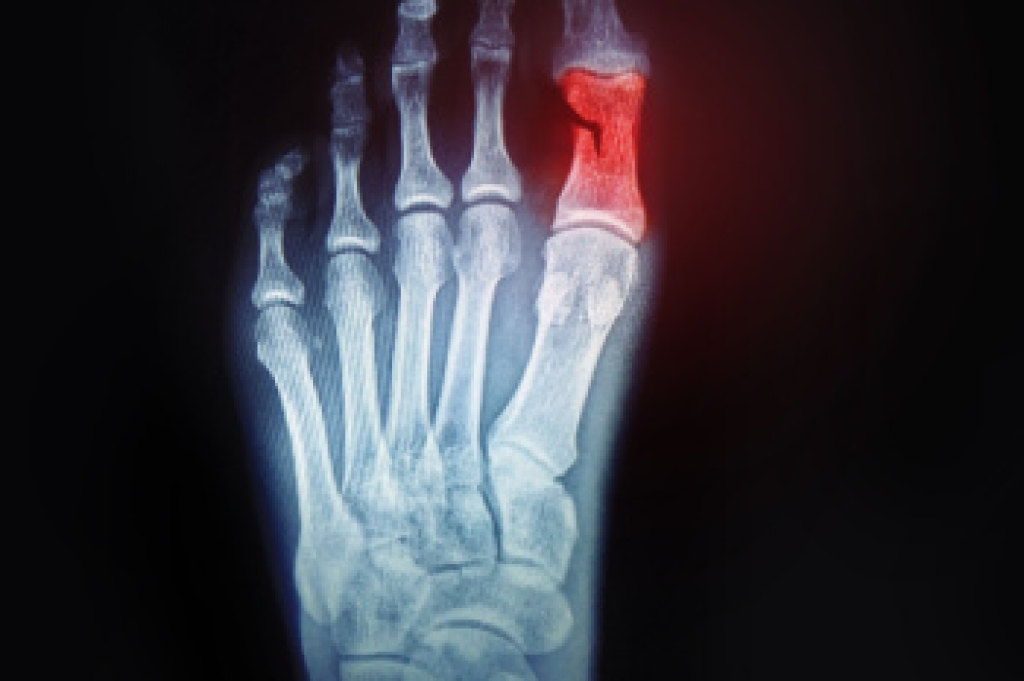

- Removing foot deformities like bunions and bone spurs

- Severe arthritis that has caused bone issues